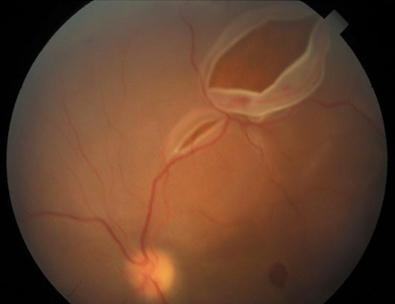

If you have a retinal detachment or a tear in the retina, those can be, not life threatening, but vision threatening symptoms. Vitreous floaters may occur following a retinal tear, retinopexy, scleral buckling, or vitreous hemorrhage associated with a tear, said gaurav k. A detached retina has to be examined by an ophthalmologist right away. Otherwise, you could lose vision in that eye. Shah, md, with the retina institute in st. Mar 28, 2020 · a retinal tear can lead to fluid and blood collecting in the eye, which can cause the development of several new floaters and loss of vision if the tear leads to a retinal detachment. Sep 18, 2020 · had a retinal tear or detachment in your other eye; People who are very nearsighted (high myopes) are at greater risk of developing floaters earlier in life and are also at a greater risk of a retinal tear or detachment.

Mar 28, 2020 · a retinal tear can lead to fluid and blood collecting in the eye, which can cause the development of several new floaters and loss of vision if the tear leads to a retinal detachment.

Mar 31, 2017 · if you have a rhegmatogenous retinal detachment, you have a tear or hole in your retina retinal tear. Shah, md, with the retina institute in st.